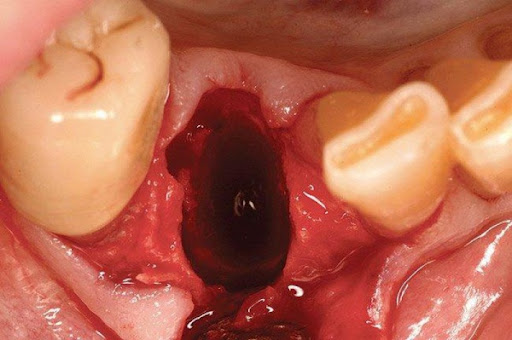

- Trong 24 giờ đầu sau khi nhổ: Tại vị trí răng bị lấy đi, máu chảy không ngừng. Triệu chứng thường gặp là các cơn đau âm ỉ, sưng, phù nề,… nướu và các mô xung quanh.

- Từ 24 đến 48 giờ đầu tiên: Cục máu đông bắt đầu hình thành trên ổ răng, giúp giữ cho lỗ không bị lắp đầy bởi các mảng bám thức ăn và vi khuẩn. Lúc này, các mô nướu mới bắt đầu hình thành bên trong lỗ và tình trạng chảy máu sẽ giảm dần và ngừng hẳn. Đau và sưng sẽ vẫn tiếp tục nhưng có xu hướng giảm dần.

Hình ảnh sau khi nhổ răng khôn

Dưới đây là một số hình ảnh lỗ sau khi nhổ răng khôn của bạn tại Nha Khoa Miền Tây: